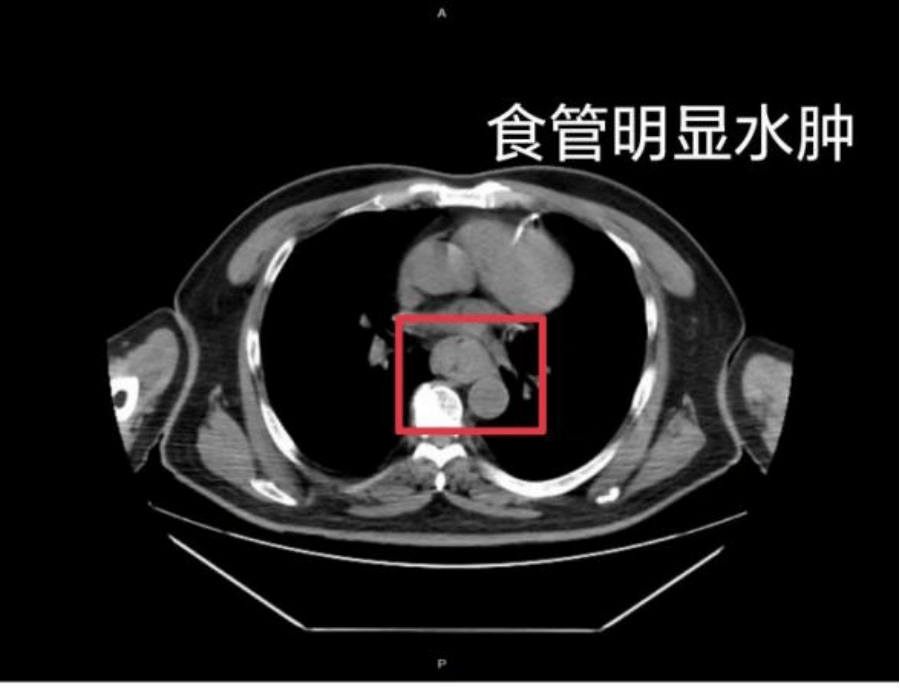

这样的情况并非个例,同样在近日,福州一位网友分享了自己因吃了一碗很烫的福鼎肉片导致呕血,并查出食管水肿的经历火币交易平台。

据网友回忆,“自己去厕所尝试呕吐时,直接呕出了血,一大口鲜血从嘴里喷出,总共吐了两次火币交易平台。”CT 结果显示,他的食管全部出现水肿损伤。